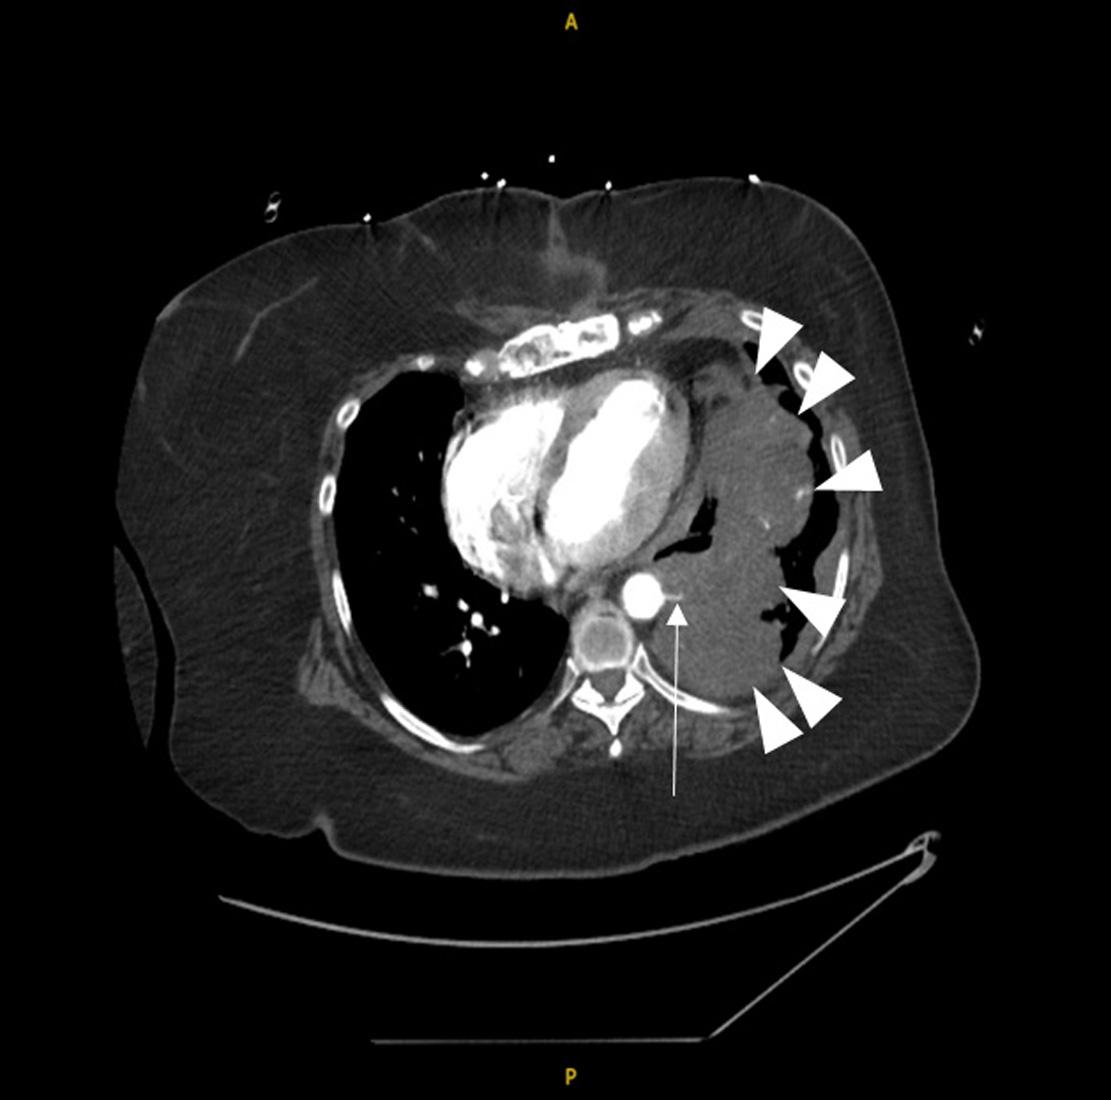

Emergentcomputedtomographyoftheabdomenand pelvisrevealedalargeleftretroperitonealandperitoneal hematomasecondarytoleftRAArupture,aswellasconcern fordevelopingsplenicinfarctsintheleftlowerrenalpole (Image).Thepatientwastakenemergentlytotheoperating room(OR)forexploratorylaparotomywithintwohoursof EDarrival.Sheunderwentsuprarenalcross-clampingwith repairoftheleftrenalarteryandligationofrenalvessels.She returnedtotheORtwodayslaterforleftnephrectomyand abdominalclosure.Shewasextubatedandtransferredtothe floor.Shewasdischargedhometwodayslaterin goodcondition.